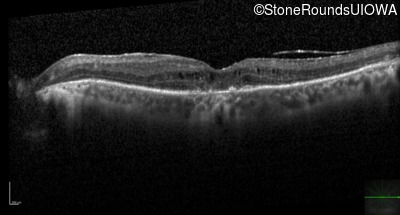

Optical Coherence Tomography - Left - 20/125

Exemplar / OCT Stack